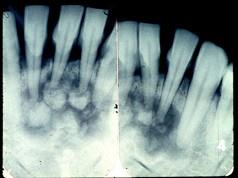

问题 图为牙骨质瘤的X?线表现,关于此病描述不正确的是()

选项 A.来源于牙胚的牙囊或牙周膜 B.肿瘤紧贴牙根部,可单发或多发 C.牙髓活力测试是阴性的 D.生长缓慢,一般无自觉症状 E.X?线显示根尖周围有不透光的阴影

答案 C